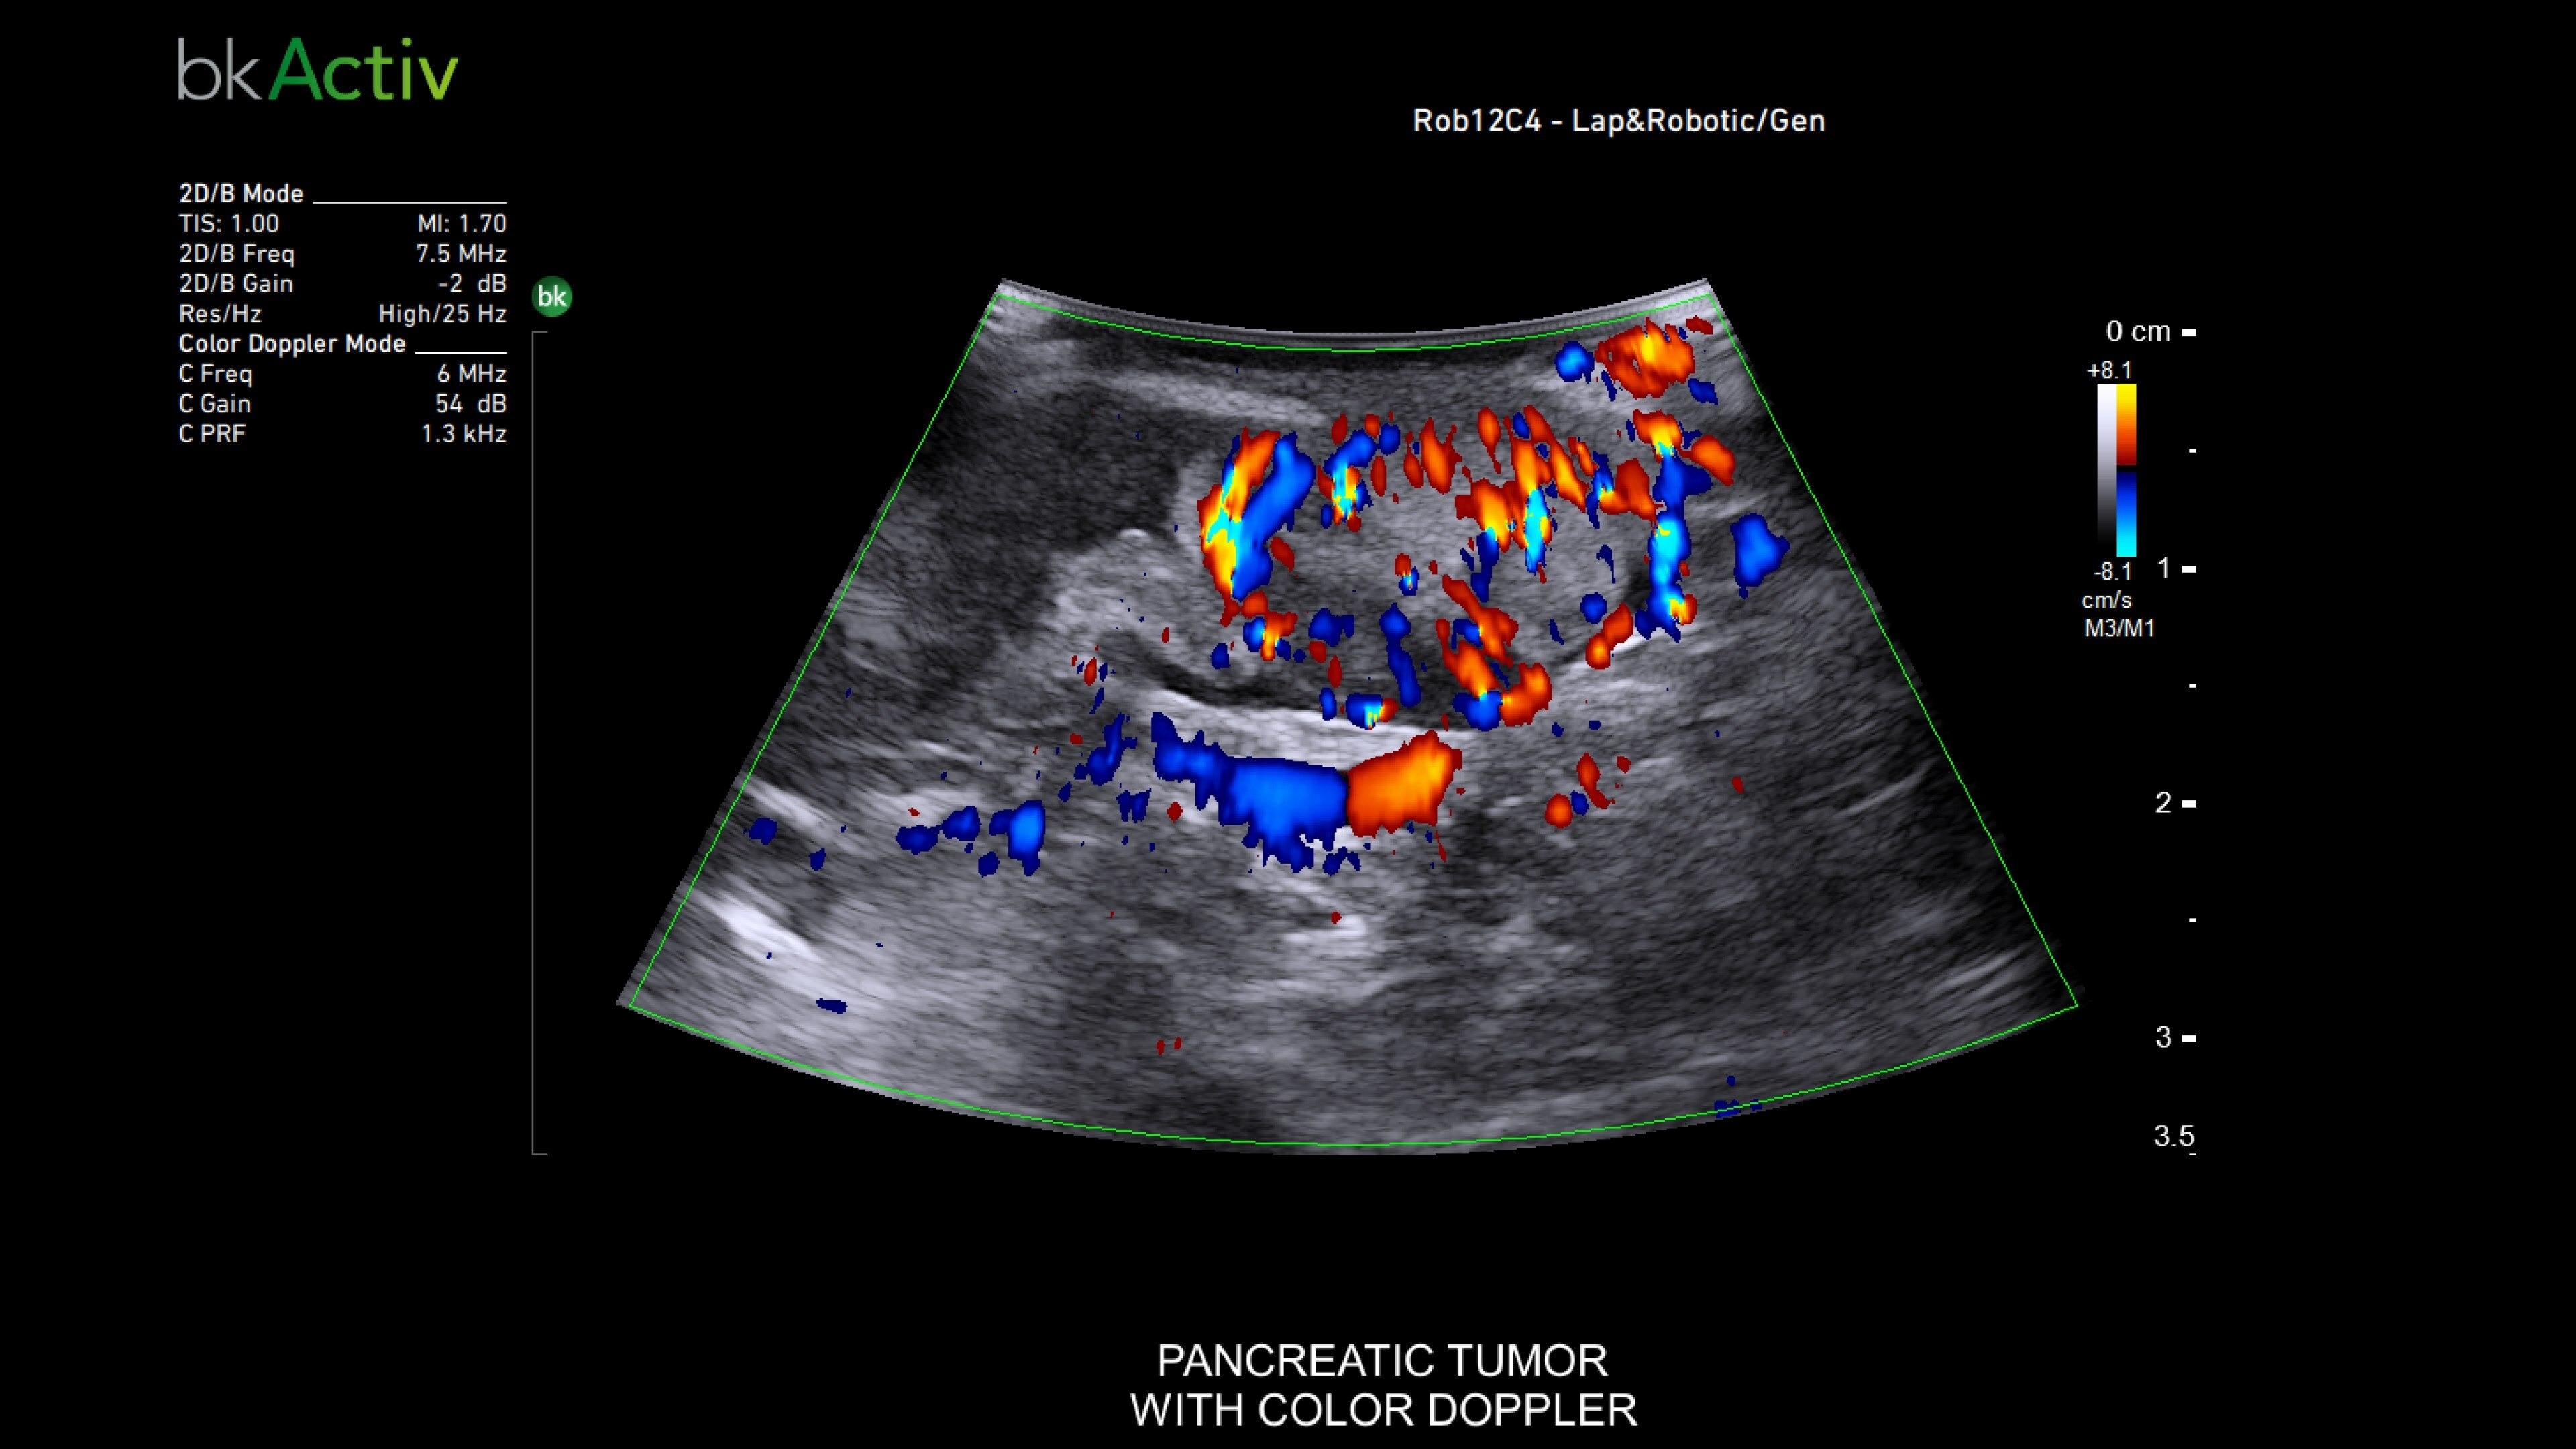

The bkActiv is a high-performance imaging system offering detailed, real-time surgical visualization. Refined through extensive research and user feedback, it supports remarkable imaging of areas of interest–neurosurgical (neuro-oncology, spine, neurovascular), urology (prostate, kidney, and bladder), hepatobiliary, colorectal, and pelvic floor.

It features technology such as Dual Live Compare for live image comparion, stored image compare, mirror image to see a live iUS image on the touch screen and sensitive color Doppler visualizes blood flow during complex surgeries.

The bkActiv ultrasound system delivers remarkable imaging for general surgery, including anorectal, robotics-assisted, and pelvic floor surgeries. Its advanced algorithms provide uniform image resolution and greater detail, while the remote control allows surgeons to adjust images within the sterile field. For anorectal surgeries, bkActiv offers high-definition imaging to visualize normal and abnormal anatomy, including anal sphincter injuries and rectal cancer. In robotics-assisted surgeries, the system's robotic transducers provide real-time, high-resolution imaging to locate and assess lesions and critical structures. For pelvic floor surgeries, bkActiv's advanced 3D architecture supports dynamic, real-time examination during procedures.